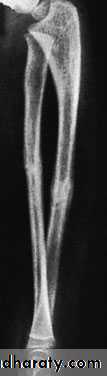

X-RAY

Both bones are broken, either transversely and at the same level or obliquely with the radial fracture usually at a higher level. In children, the fracture is often incomplete (greenstick) and only angulated.